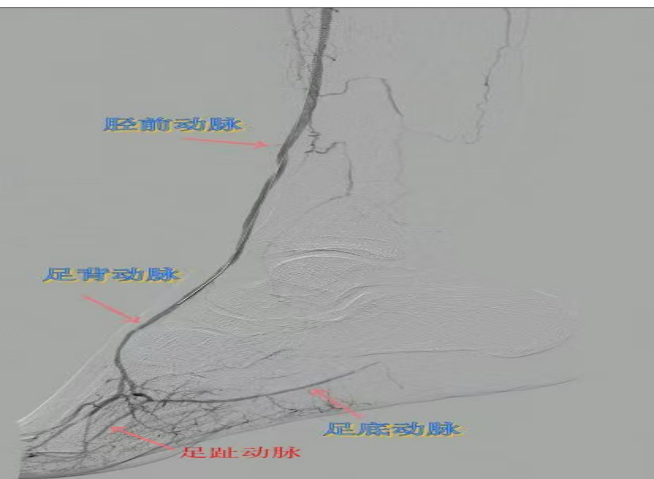

67岁女性患者,多年糖尿病、冠心病史,因右足溃烂伴凉麻疼痛长达2年就诊,此前曾接受外院介入术后血管再度闭塞。此次检查发现其股浅动脉、腘动脉至膝下血管全程闭塞,且伴有严重钙化。团队迎难而上,创新性经足背动脉逆向穿刺,耗时3小时成功贯通胫前动脉。术后当夜患者足部即感回暖,溃烂足趾疼痛显著缓解。术后结合中药外治(换药、熏洗、去腐生肌膏外敷)加速创面愈合。该患者已于出院,院外换药治疗。

78岁男性患者,糖尿病合并高血压、脑梗塞,右足持续疼痛伴冰凉发绀3个月。入院CTA显示其右侧股浅动脉全程闭塞,膝下三支动脉均闭塞。医疗团队在局部麻醉下,再次巧妙应用“逆向开通技术”,经胫后动脉——足底弓逆向开通足背动脉及胫前动脉。术后患者右足皮温即刻回升,疼痛消失。术后结合中药外治(换药、熏洗、去腐生肌膏外敷)加速创面愈合,患者已顺利出院。